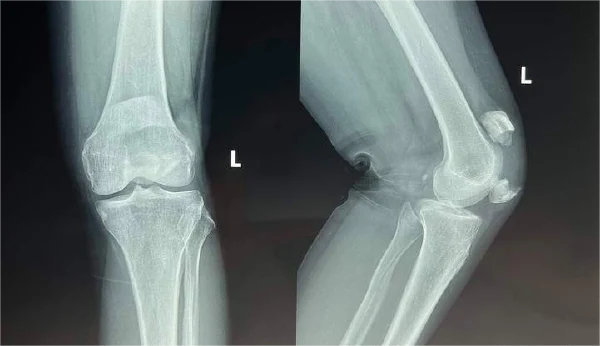

髌骨位于膝关节前部,对于膝关节的正常功能至关重要。当髌骨发生骨折时,患者通常会出现膝盖前部的剧烈疼痛、肿胀,甚至无法站立或行走。这种骨折可分为简单骨折和粉碎性骨折,简单骨折通常仅有一条骨折线,而粉碎性骨折则骨折线多且破碎严重。

针对髌骨骨折的治疗方法多种多样,取决于骨折的严重程度和患者的具体情况。保守治疗和手术治疗是常见的两大类方法。《柳叶刀》中的一项研究指出,对于不需要手术的简单骨折,通常采用保守治疗的方法,包括使用石膏固定、理疗和药物治疗等。

然而,对于粉碎性髌骨骨折或合并关节错位的病例,手术治疗往往是最佳选择。据《新英格兰医学杂志》报导,手术方式包括髌骨的切开复位和内固定术等。手术后,患者通常需要进行一段时间的康复治疗,以恢复膝关节的功能。